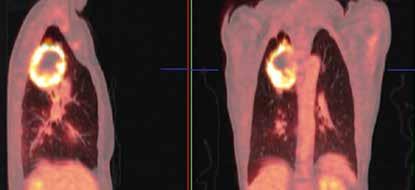

Longfoto en CT-scan van een 62-jarige patiënte die rookt en sinds enkele weken bloed ophoest. Ter hoogte van de bovenste kwab van de rechterlong is een massa te zien.

De PET-scan laat zien dat de massa verdacht is. Een biopsie bevestigt vervolgens het vermoeden van longkanker.